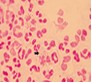

淋病的癥狀有哪些?陜西省老醫(yī)協(xié)男科指出:淋病(Gonorrhea)是淋病奈瑟菌(簡稱淋菌)引起的以泌尿生殖系統(tǒng)化膿性感染為主要表現(xiàn)的性傳播疾病。是一種古老而又常見的性病。近年來發(fā)病率居我國(中國)性傳播疾病首位,淋菌為革蘭氏陰性雙球菌,呈腎型,成雙排列,離開人體不易生存,一般消毒劑容易將其殺滅。多發(fā)生于青年男女。那么淋病的有哪些癥狀表現(xiàn)呢?下面我們來具體說說。